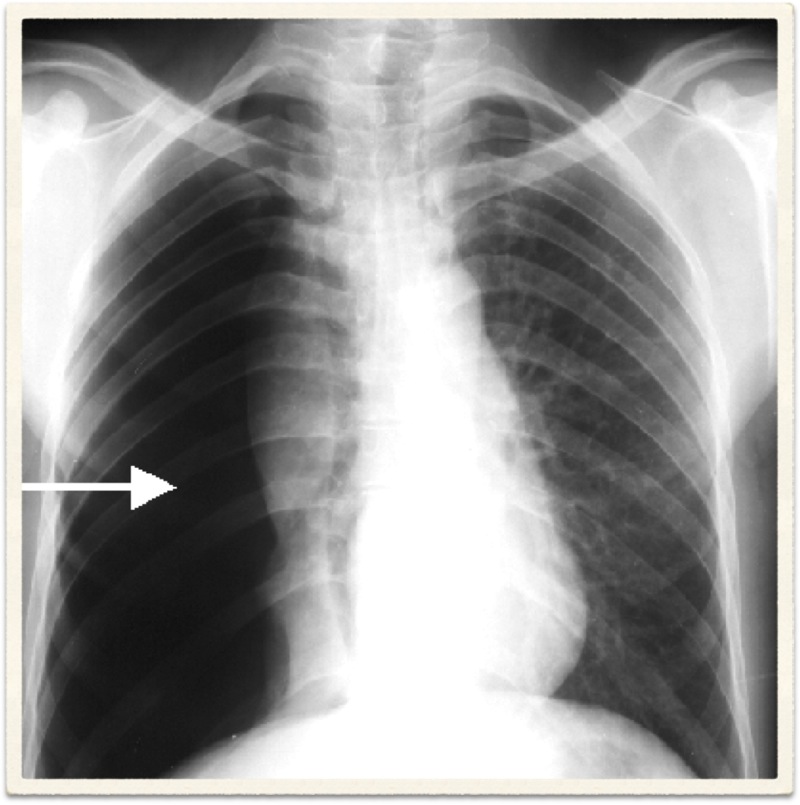

Radiological Report: Cardiac size within normal limits. Both lungs show severe overinflation typical of COPD. No sign of mass or consolidation.

Hyperinflation secondary to emphysema

Chronic bronchitis cannot be diagnosed radiologically. Although findings such as increased lung markings or tubular opacities, bronchial wall cuffing (thickening) can be seen with bronchitis, they are nonspecific. The main reason for getting a chest X-ray is to exclude other conditions, such as bronchiectasis, which can mimic the disease clinically.